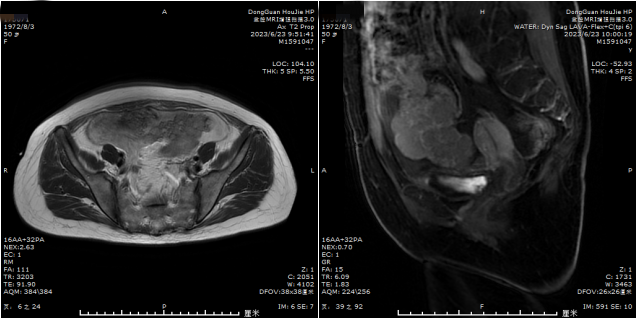

不查不知道,一查吓一跳,这次检查竟然查出盆腔巨大包块考虑恶性肿瘤广泛转移可能。入院CT提示:①卵巢癌并腹膜多发种植转移,腹盆腔多发积液;②肝囊肿;③拟胆囊息肉。经妇科会诊后,转入妇科接受进一步治疗。

完善系统检查及经过穿刺放腹水,术前纠正低蛋白血症提高术前机体状态,根据术前检查诊断双侧卵巢恶性肿瘤IIIC期,腹膜多发转移,盆腔大量积液。吕晓亮向韦女士及家属解释病情:这种情况可以手术治疗,并告知我院与孙逸仙纪念医院开展了医联体合作,听完后韦女士要求在我院接受手术治疗。

术中见:肝、脾表面光滑,右侧膈肌表面见肿瘤赘生物大小约9*8*7cm,呈柄状,左侧膈肌腹膜表面见粟粒样肿瘤赘生物,直径0.3-0.5cm,左侧横膈腹膜、盆腔腹膜、两侧结肠旁沟腹膜、肠系膜见粟粒样肿瘤赘生物,直径0.3-0.5cm,腹膜、结肠、小网膜表面可见明显肿瘤赘生物,直径约0.2~2cm左右,大网膜见肿瘤赘生物大小约8*7*6cm呈柄状,余大网膜表面见粟粒样肿瘤赘生物,直径0.3-0.5cm。子宫萎小,表面布满肿瘤结节,后壁与结肠粘连,为肿瘤侵润,封闭直肠窝;前壁与膀胱粘连,肿瘤组织呈厚苔样附着、粘连于膀胱表面。右侧卵巢约10.0×5.0×4.0cm,为囊实性包块;左侧卵巢约7.0×4.0cm;双侧输卵管约3×0.5cm,浆膜面见粟粒样肿瘤赘生物。乙状结肠、直肠表面见肿瘤赘生物大小约8*8*6cm,阑尾无肿大,表面见粟粒样肿瘤赘生物;髂内外及闭孔淋巴结未扪及肿大。